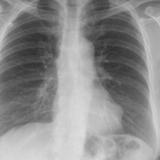

Case 4a

Peric effusion

Date: 03/17/2004

Views: 2989